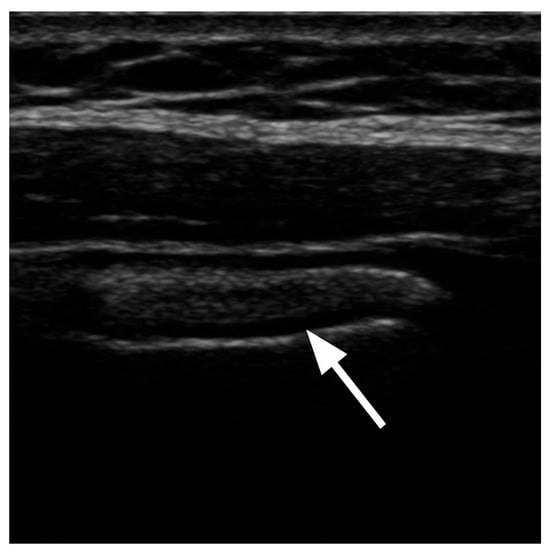

5. Visualization and Imaging Studies